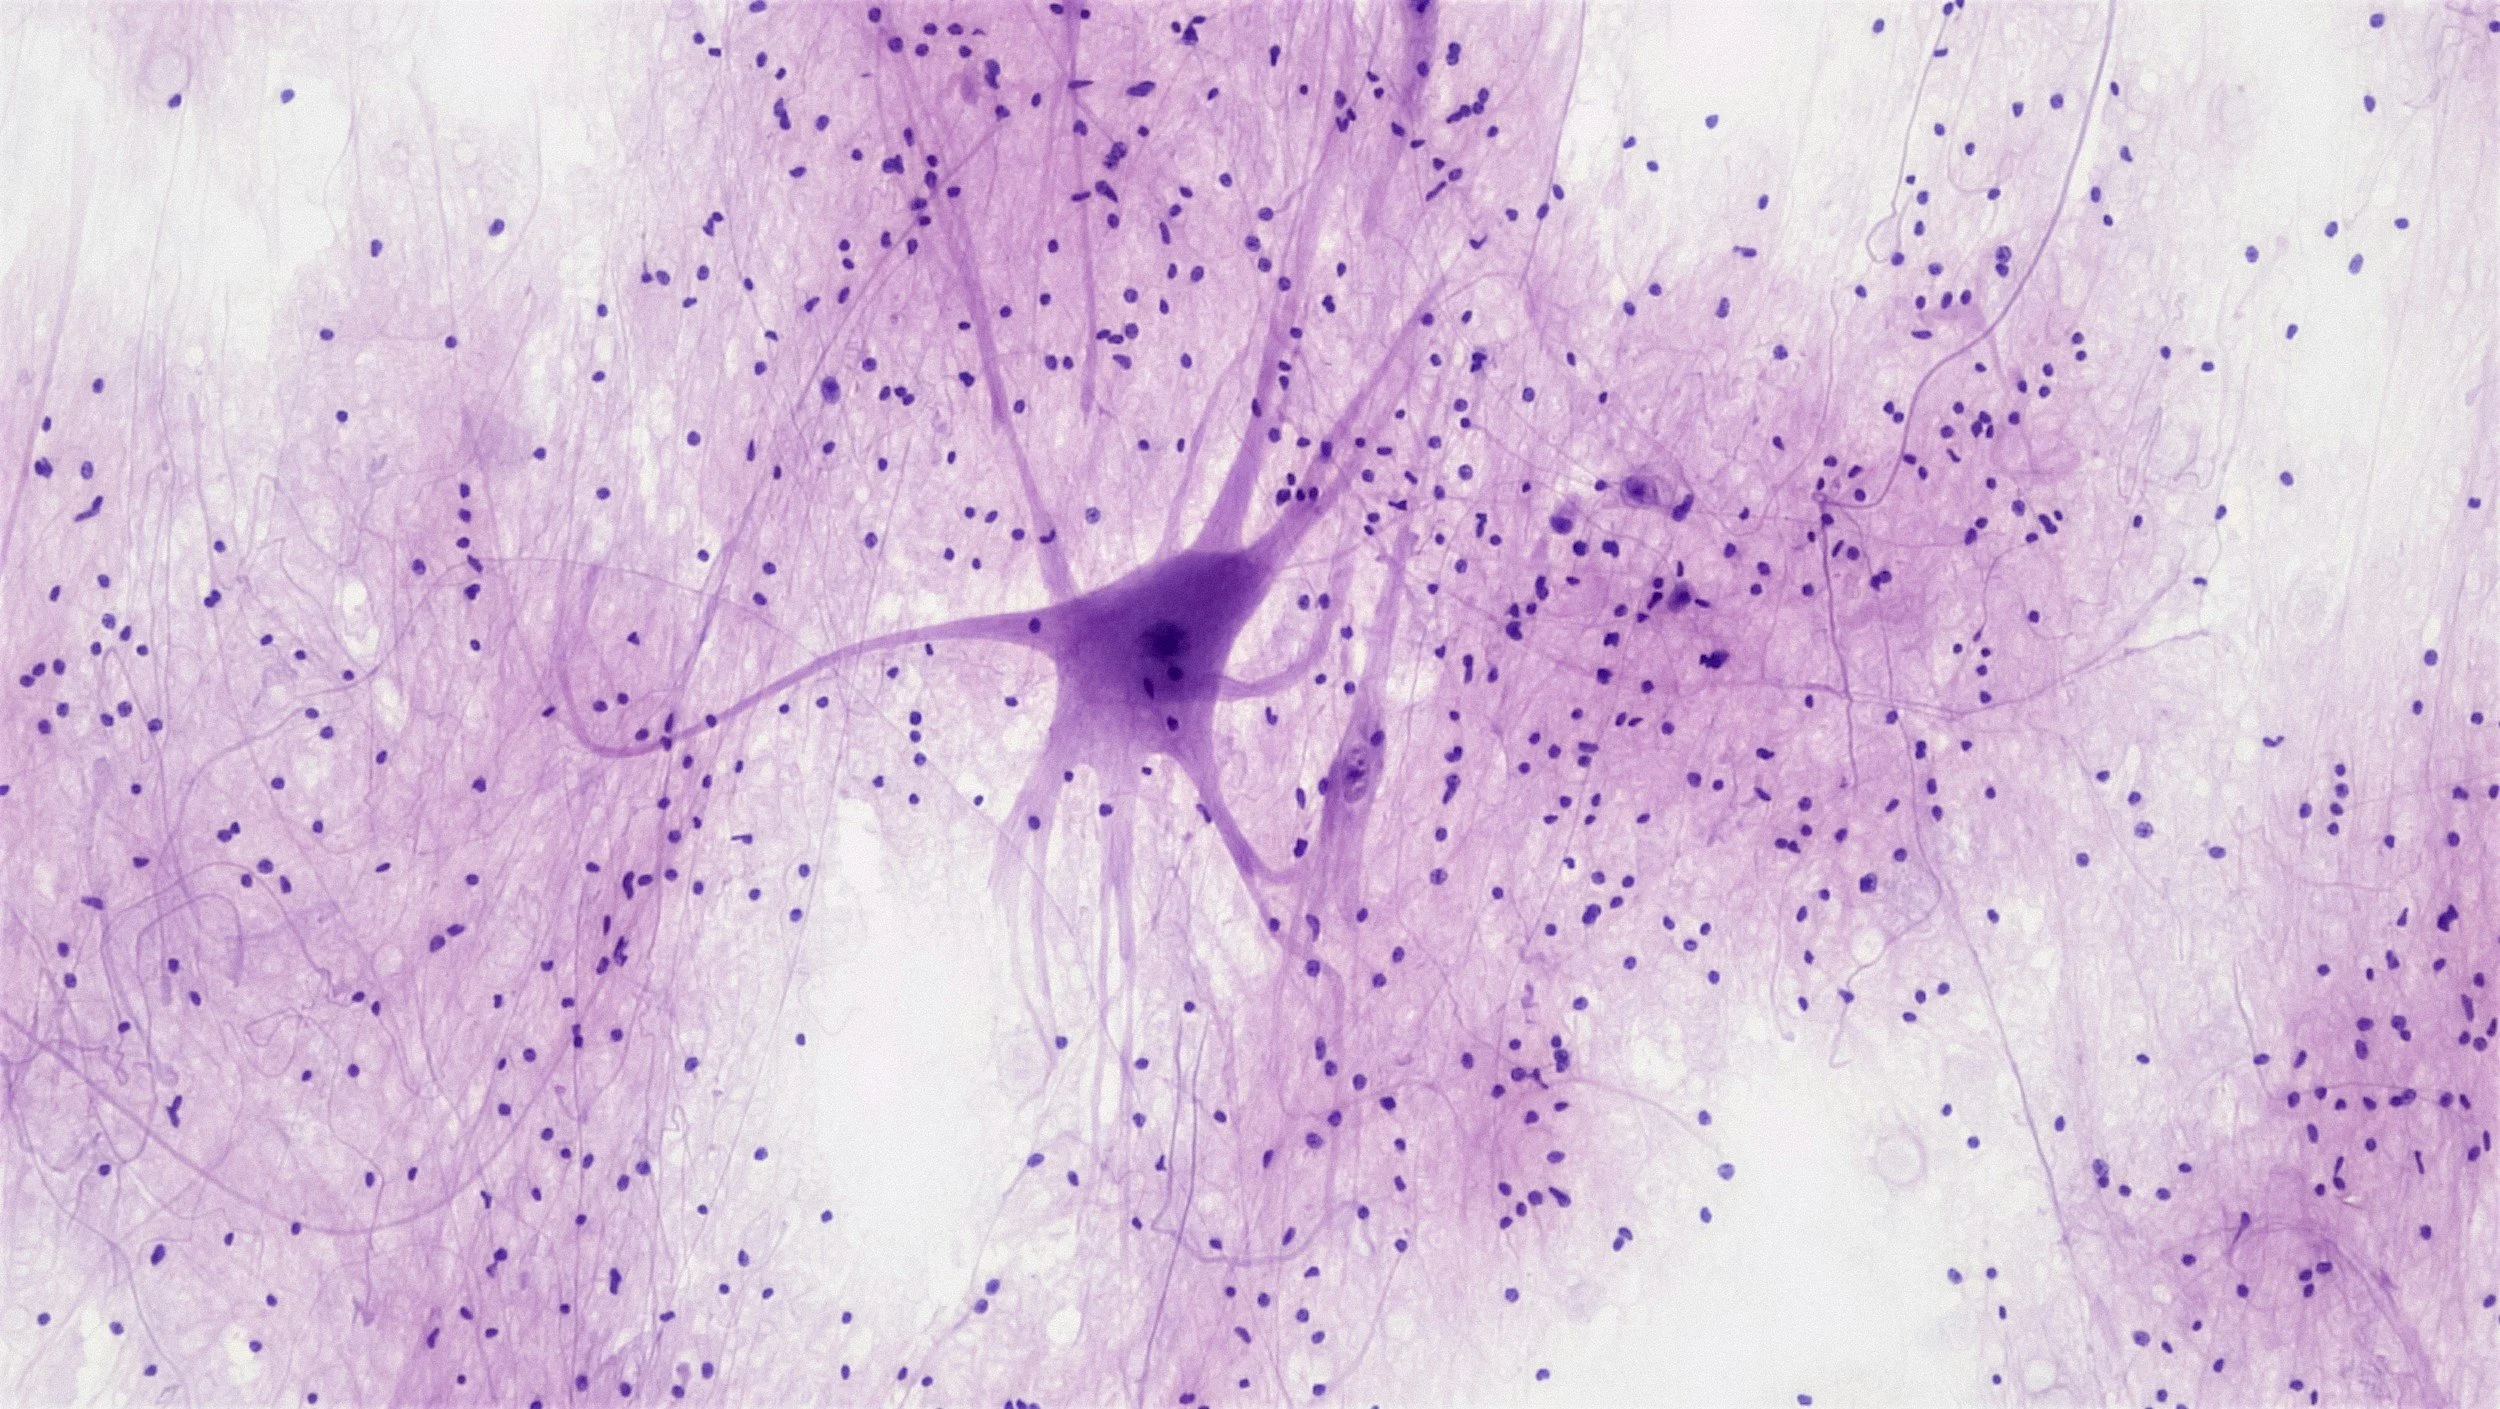

We will examine the role of the autonomic nervous system in symptoms related to PTSD. We will discuss how these symptoms manifest, how to measure the underlying physiological factors, and how to address them to foster feelings of relaxation and safety in populations affected by PTSD.